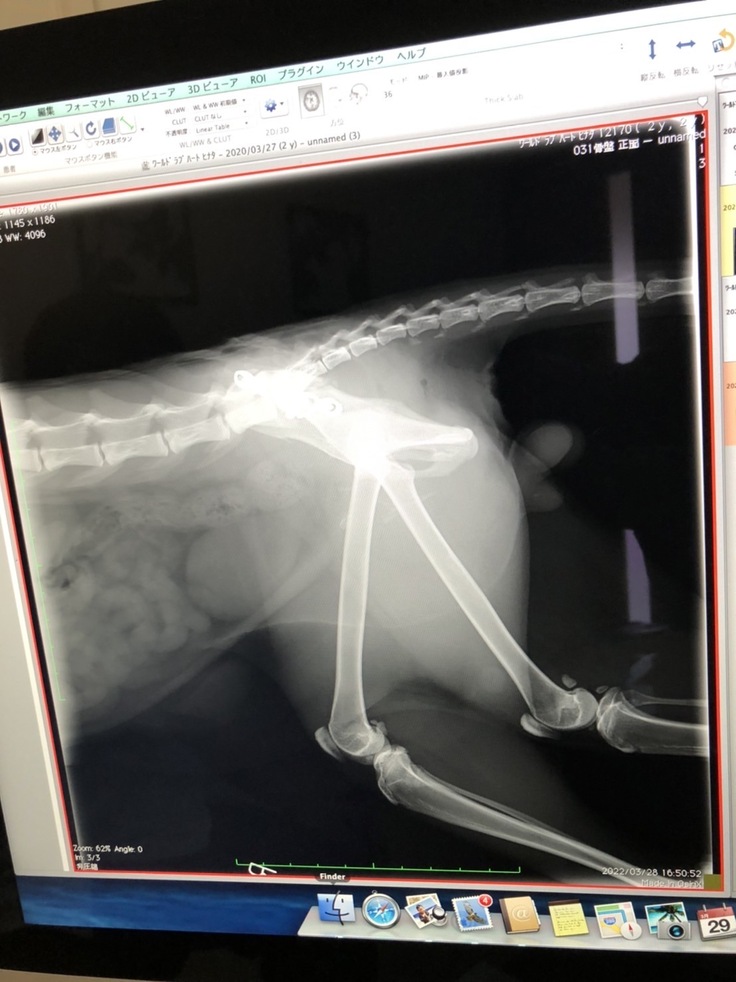

手術内容 ⑴骨盤骨折:右腸骨体骨折はプレート固定、左仙腸関節脱臼は元の場所に戻してスクリューで固定してもらいました。 ⑵右大腿骨頸部骨折:事故から2週間以上経っていて治ってきているのでこのまま自然治癒という形をとります。将来関節炎になる可能性があるとのこと。大変な手術でしたが、日向は頑張りました。病院でも看護師さんになつき、順調な回復を見せました。

手術後のレントゲン写真と日向